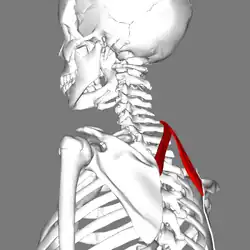

Le muscle petit rhomboïde est un muscle pair du dos reliant l'épaule au rachis.

Le muscle petit rhomboïde forme la partie supérieure du muscle rhomboïde et est situé sous le muscle trapèze.

Le muscle petit rhomboïde nait des processus épineux de la septième vertèbre cervicale et de la première vertèbre thoracique, ainsi que du bas du ligament de la nuque.

Le muscle petit rhomboïde se dirige obliquement en bas et latéralement.

Le muscle petit rhomboïde se termine sur le bord médial de la scapula, au niveau de la racine de l'épine scapulaire (au-dessus du muscle grand rhomboïde).